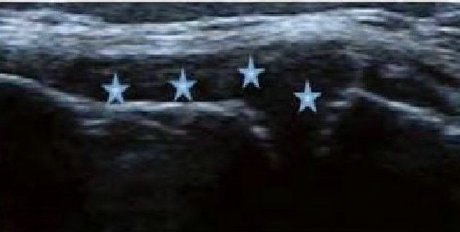

• 肌骨超声检查发现RA软骨侵蚀、骨质受损

患者类风湿未坚持治疗,膝关节肿大无法行走,经肌骨超声检测出膝关节软骨表面毛糙、凹凸不平,回声大幅增高,局部软骨变薄渐趋消失。判定RA骨质受损严重。